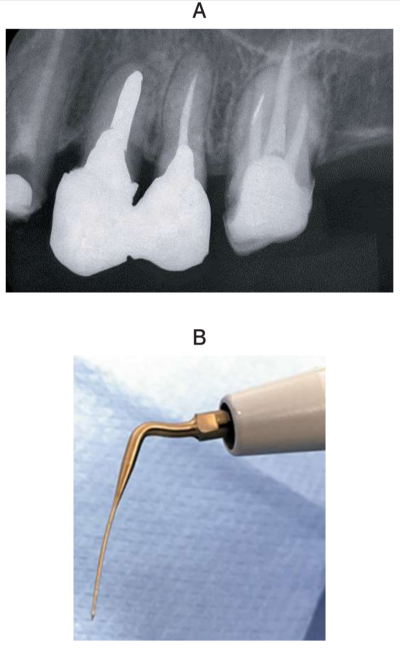

60 歳の女性。上顎左側第一大臼歯の咬合痛を主訴として来院した。検査の結果、歯内治療を行うこととした。根管充塡材を除去したが、近心頰側根は途中でファイルが進まなくなり、根尖まで穿通できなかった。術前のエックス線画像と次に用いる器具の写真を別に示す。

この器具の使用目的はどれか。2つ選べ。